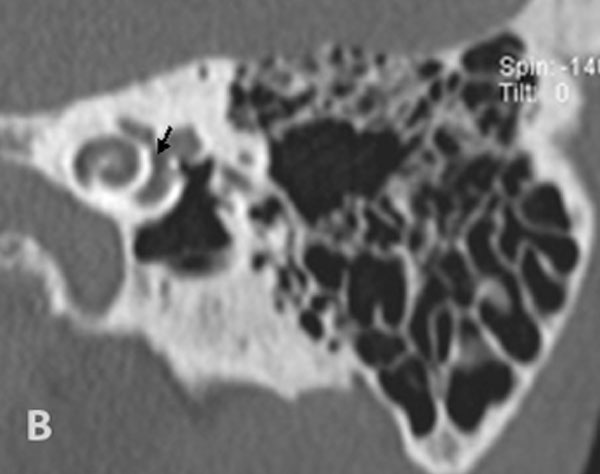

TC de alta resolução. Doente com vertigens pós-estadectomia. Reconstrução em Pöschl (A) e Stenvers (B). As setas referenciam a ponta do pistão de titânio na janela oval, discretamente afundado.